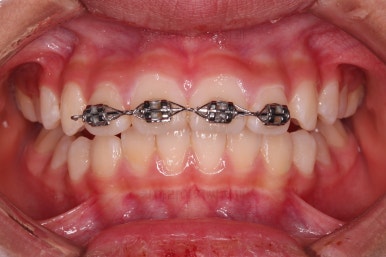

부산소아교정 마무리 사진입니다.

프리올소로 유지과정까지 총 2년 3개월 가량 걸렸고요.

이정도 마무리면 굳이 2차교정까지 안해도 되겠죠?

정교한 조절은 안했지만 치열이나 교합/맞물림 등 매우 좋아졌습니다.